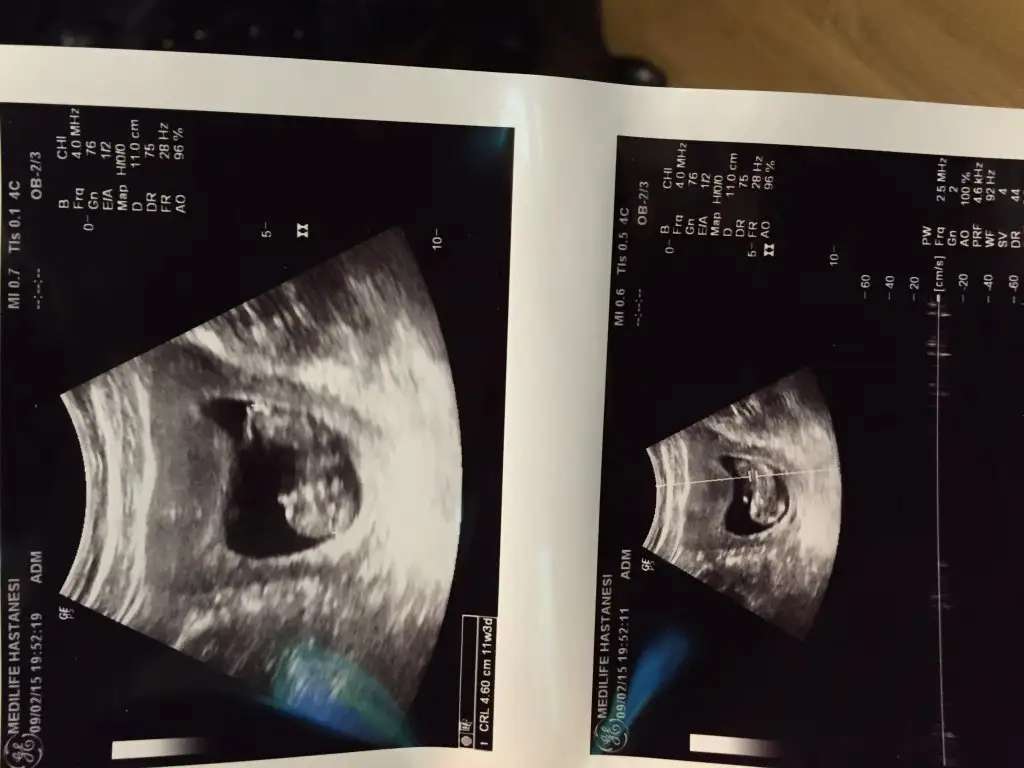

dr soylemeden siz gorun genital nub teorisi ( bebegin cinsiyeti)

kızlar bilenler yardımcı olabilir mi :)

bendee çok merak ediyorum ama tahminim kız net orta da eşimde erkek diye çok heveslendi ama olmayacka gibi 3 hafta sonra ögrenicem

yook belli değil benim nub teorime göre kız :KK64: bide doktorum kıza benziyor dedi. ama kemik gelişimi erkek dedi kesin demiyorum dedi diğer geldiğinize kesinleştiririm dedi.